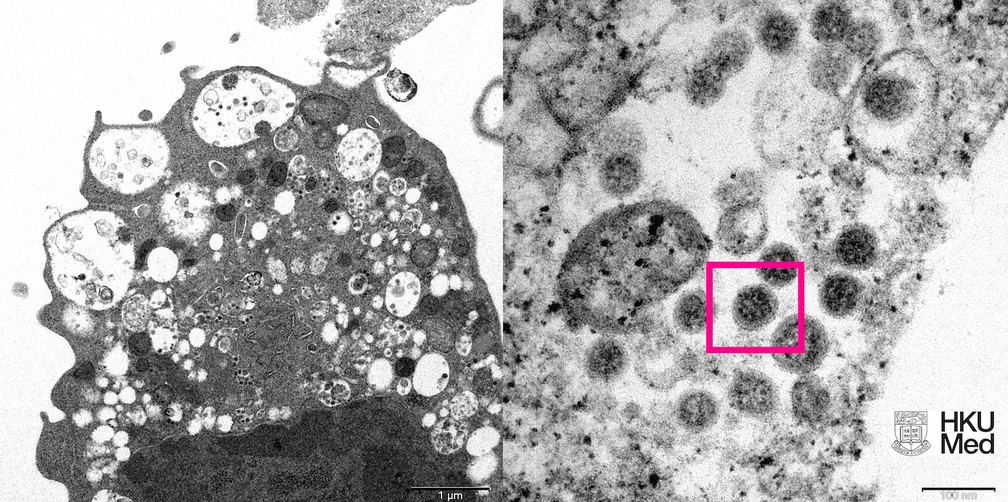

Cientistas da Universidade de Hong Kong conseguiram capturar pela primeira vez a imagem da variante ômicron do coronavírus com a ajuda de um microscópio, informou a instituição em um comunicado na quarta-feira (8).

Os pesquisadores da Faculdade de Medicina divulgaram dois registros – de microscópios eletrônicos – de uma cultura do vírus em laboratório. Veja a FOTO acima.

Na imagem da esquerda, explicam os cientistas, é possível ver um recorte “de baixa ampliação” de uma célula de rim de macaco infectada intencionalmente com essa variante do Sars-Cov-2.

Nela, é possível ver que a ômicron provoca danos em nível celular com vesículas – essas pequenas bolhas – cheias de pequenas partículas virais (identificadas pela cor preta).

Já na imagem da direita, a micrografia eletrônica tem alta ampliação desta mesma célula, mas mostrando as partículas virais mais de perto (dentro deste quadrado cor de rosa).

Neste registro, é possível inclusive ver a coroa do coronavírus (formada pela proteína S) ao redor da partícula viral.

A imagem foi produzida pelos professores John Nicholls, Malik Peiris e Tam Wah-Ching da Universidade de Hong Kong.